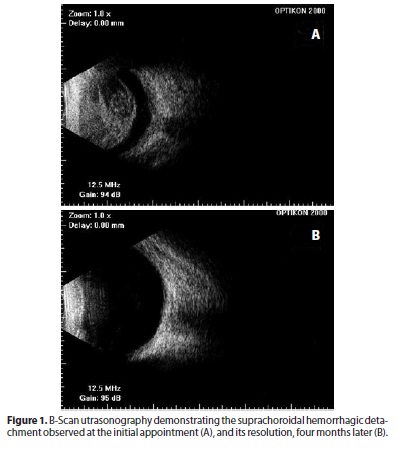

Right eye visual acuity was light perception and intraocular pressure was 49 mmHg in the same eye. At biomicroscopy, anterior chamber was narrowed, pupil was immobile, and an intraocular lens was observed. Fundus examination revealed choroid detachment involving the ciliary body. Hemorrhagic detachment was detected with B-scan ultrasonography (Figure 1A). Except for nuclear cataract, the left eye was normal.

Right eye visual acuity was 20/50 and 20/20 after two and four months, respectively. Except the immobility of the pupil initially observed, all the pathological bleeding had disappeared. B-scan ultrasonography and composite fundus photograph (Figure 1b and Figure 2) revealed resolution of the hemorrhagic detachment.